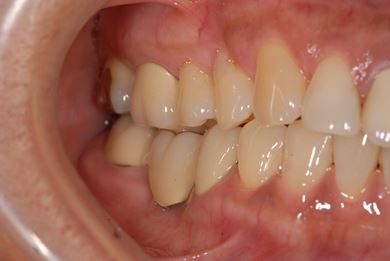

骨再生インプラント治療+セラミック治療+歯肉歯槽骨整形手術

| 治療内容 | インプラント2本(ソケットリフト、GBR)、メタルボンドセラミッククラウン3本、歯肉歯槽骨整形手術 | ||||||||||||||||||||||||||||||||